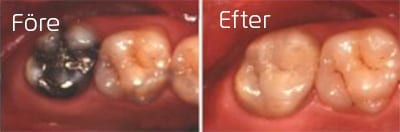

Porslinsonlay på kindtand

Amalgam på sista kindtanden ersatt med porslinsfyllning (onlay)